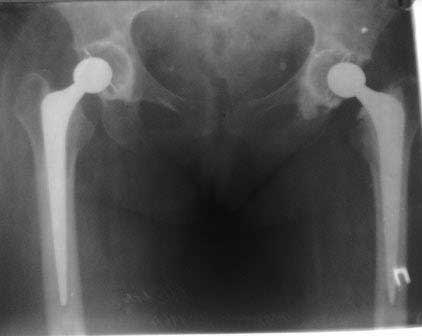

В дополнение к моему вышеуказанному пациенту. Досылаю послеоперационный снимок, который я не выслал сразу.

Нет вы не поняли! Вы поспешили с выводом! Я не смог выслать окончательный, послеоперационный снимок, по техническим причинам. Я это сделал позже, что Вы и видите ниже! Извините, если я Вас запутал!

С последним, третьим снимком он ко мне и обратился, после чего он был и прооперирован на правом тазобедренном суставе!

Эндопротез Ножка Cerafit компании Ceraver- чашка той же компании.

Расшорошили вертлужную впадину (дебридмент) Заменили чашку,учитывая невозможность полностью исключить инфекционный генез нестабильности, установили вертлужный компонент цементной фиксации (цемент с ванкомицином), поменяли головку из-за изменившихся взаимоотношении между бедренным компонентом и новой чашкой. Рану зашили наглухо. Провели антибактериальную терапию Кубицином. Выписали на 10 сутки после операции. Болевой синдром купирован, пациент радостный, уехал к себе в Калугу. Приедет на контрольный осмотр через месяц.